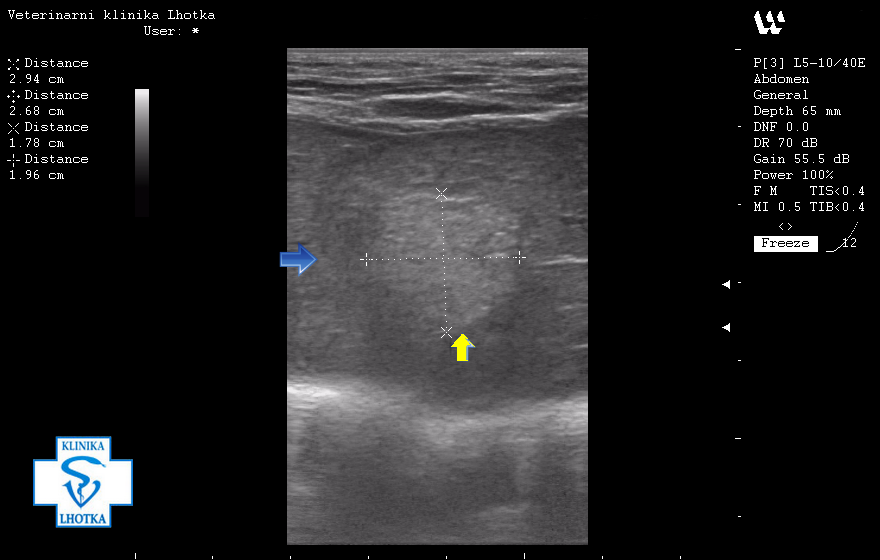

Na ultrazvukových snímcích jsou šipkami označeny metastázy v oblasti jater, levé ledviny, pravděpodobně i v močovém měchýři a v mízních uzlinách pod bederní páteří.

Na tomto obrázku modrá šipka odděluje normální strukturu jater od metastáze. Střed útvaru má jinou strukturu, než nepostižená jaterní tkáň (žlutá šipka).

SONO jater - metastáza nádoru mléčné žlázy1